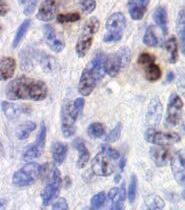

Per l'esperimento successivo abbiamo suddiviso gli animali non in grado di produrre la propria vitamina C in due gruppi. Poi agli animali di entrambi i gruppi è stato inoculato il cancro della pelle (melanoma). In seguito, un gruppo è stato sottoposto ad una dieta contenente una quantità ottimale di vitamina C, mentre l'altro gruppo ha ricevuto una dieta carente di questo nutriente essenziale.

Nella pagina a fianco sono riportati gli incredibili risultati documentati per la prima volta in questo esperimento. Gli animali con carenza di vitamina C nella dieta sviluppano tumori di grandi dimensioni, che crescono sempre più diffusamente nei tessuti limitrofi (figura A). Al contrario, gli animali con una dieta ricca di vitamina C hanno sviluppato meno tumori e tumori più piccoli. Cosa ancor più importante, in questo gruppo un quantitativo ottimale di vitamina C nella dieta ha portato alla formazione di tessuto connettivo di confinamento (incapsulamenti) dei tumori (figura B). Questo esperimento dimostra che la presenza o l’assenza di vitamina C è un fattore decisivo per stimolare la difesa del corpo contro i danni del cancro.

AA. Un tumore cancerogeno sviluppato in un topo, non in grado di produrre vitamina C che viene sottoposto ad una dieta carente di vitamina C.

Notare che il confine diffuso del tumore (freccia) con le cellule tumorali che facilmente invade i tessuti circostanti

BB Con l’integrazione di vitamina C, i topi dello stesso esperimento hanno eretto una forte barriera di tessuto connettivo attorno al tumore, confinandolo alla posizione originale E' evidente da questa immagine che è improbabile che i tumori incapsulati invadano il tessuto circostante e creino una metastasi.